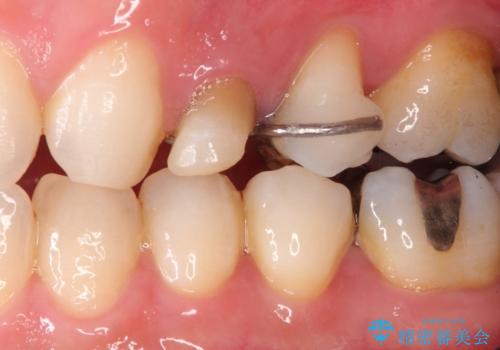

- 歯肉の下まで深く歯が折れたことを主訴に来院された患者様です。

かかりつけ医にて応急的に修復してますが根本的な治療を希望され、矯正的挺出を行ったのち、歯周外科を行い、歯冠修復をしております。

歯肉縁下の水平破折をきちんと治療するためには時間も費用もかかります。